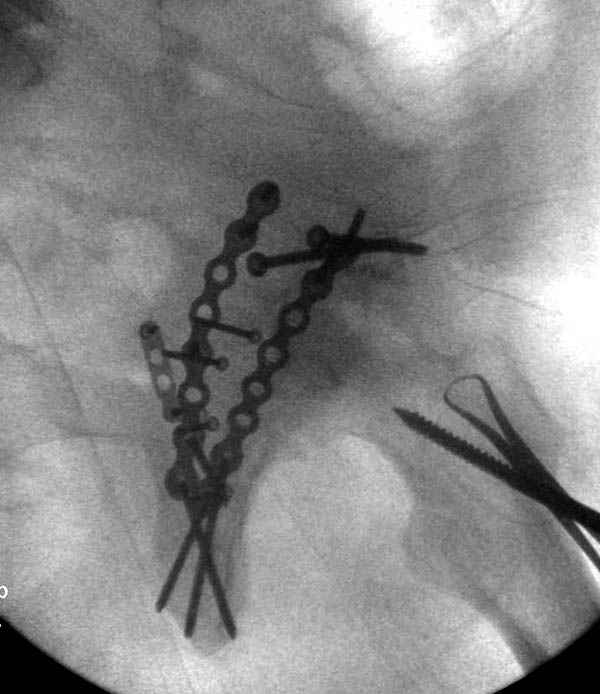

Там множество обычных 2.7 мм шурупов, потом идет фиксация основными пластинами.

Снимки здесь....